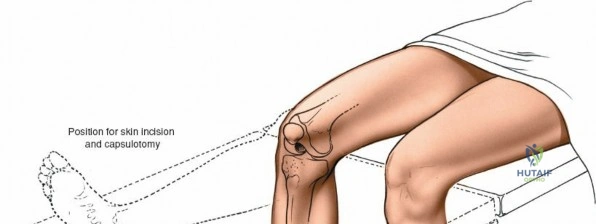

- Supine Position: The patient is positioned supine on the operating table. This allows for excellent access to the anterior aspect of the knee.

- Patellar Position: The knee should be slightly flexed (15-30 degrees) or in full extension initially to facilitate the skin incision. Adjustments will be made throughout the procedure. Adequate padding for the heels, sacrum, and upper extremities is crucial to prevent pressure injuries. The ipsilateral hip may be slightly abducted and externally rotated for optimal surgical field ergonomics.

1. Skin Incision

The incision typically begins approximately 3-5 cm proximal to the superior pole of the patella, curves slightly medially along the patellar border, and extends distally parallel to the medial border of the patellar tendon, terminating approximately 2-3 cm distal to the tibial tubercle. A straight midline longitudinal incision is an alternative, particularly when combined with a medial parapatellar capsular approach for TKA, offering a large exposure. The length and curvature of the incision are tailored to the specific procedure and patient anatomy.

Initial skin incision marked, extending proximally along the quadriceps, medially to the patella, and distally along the patellar tendon.